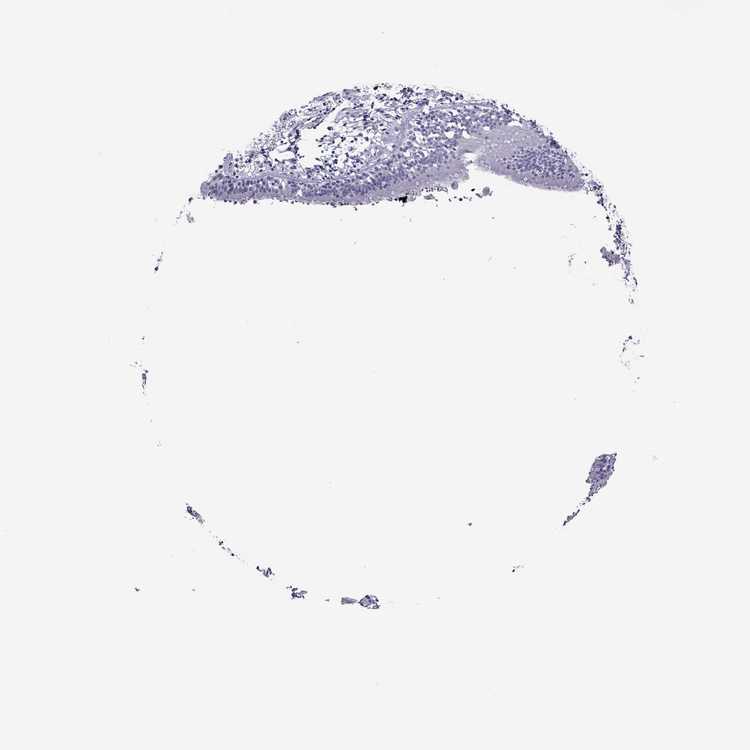

SOFT TISSUE 1 - Antibody stainingi

Antibody staining in the annotated cell types in the current human tissue is reported as not detected, low, medium, or high, based on conventional immunohistochemistry profiling in selected tissues. This score is based on the combination of the staining intensity and fraction of stained cells.

Each image is clickable and will lead to virtual microscopy that enables deeper exploration of all samples and also displays staining intensity scores, fraction scores and subcellular localization as well as patient and tissue information for each sample.

Antibody HPA072129

Chondrocytes Not detected

Fibroblasts Not detected

Peripheral nerve Not detected